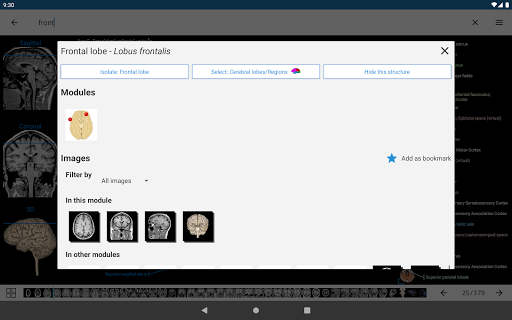

*Improved detail view of anatomical parts for easier identification in images of the current and other modules.

-Within the details view of an anatomical structure, a pin now points the related structure in all present images

Also tap directly on the image to navigate to the presented image in that module

- “Filter by”, in the details view you can now filter the images containing the anatomical structure by modality

- “Filter by”, in the details view you can now filter the images containing the anatomical structure by modality